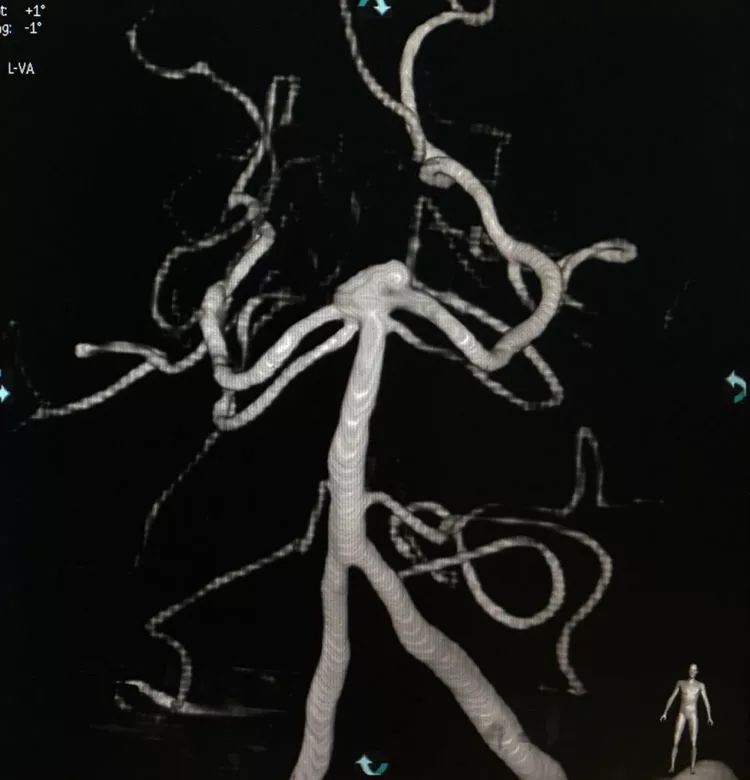

左椎动脉造影三维重建和测量

Sychro14微导丝携Headway21支架导管经左椎动脉-基底动脉进入右侧PCA,因瘤颈主要累及右侧PCA,故计划支架跨基底动脉顶端动脉瘤释放于右侧PCA-基底动脉内。